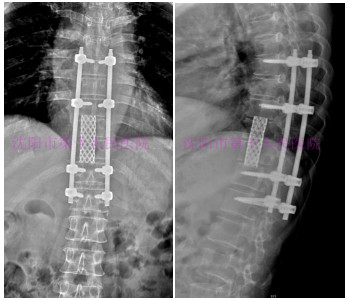

术后DR提示:脊柱侧凸畸形矫正,脊柱序列整齐。

术前DR:内固定及钛网位置满意